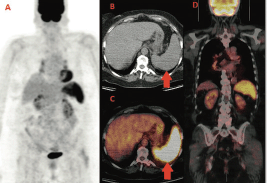

We report the case of a 60-year-old woman diagnosed with left breast cancer in 2006. The histology showed an oestrogen (ER) and progesteron (PgR) receptor positive, HER2 negative, invasive lobular carcinoma, with some palpable left axillary nodes. The staging CT scan showed multiple mediastinal and abdominal lymph nodes. The patient was asymptomatic. Considering her breast cancer as metastatic, she received surgery on the primary tumour and axillary nodes but no radiation treatment and started palliative letrozole. The breast cancer’s stage was established as pT1c N3 M1. She was followed with clinical, biochemical evaluations and an annual CT scan that always showed stable disease. In the late 2013, for the first time, a 18F-FDG PET-CT was performed for disease status assessment. Images were acquired one hour after intravenous injection of 240 MBq (6.5 mCi) of 18F-FDG according to the body mass index. Maximum-intensity projection PET image (A), axial CT (B), and fused PET/CT images (C,D) (Figure 1) showed intense and diffuse tracer uptake in the spleen (red arrow), which had an homogeneous parenchymal structure without focal nodular lesions and, in mediastinal field, multiple FDG avid bilateral hilar lymph nodes characterised by greater lymph node enlargement on the right side.

Figure 1. First F-FDG performed; intense and diffuse tracer uptake in the spleen and hilar lymph nodes.